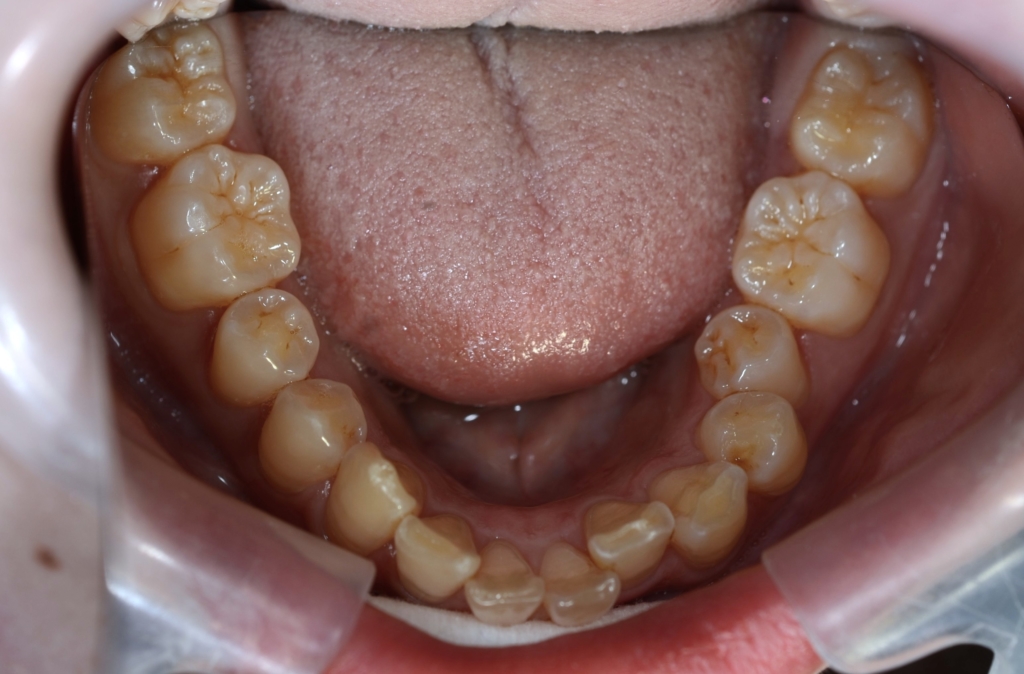

【Before】

レントゲン写真を確認すると、

この患者さんの場合、

【診断】

#1.上顎前突

#2.顎と歯の大きさの不調和による叢生

#3.ガミースマイル

と診断しました。

*歯並びの写真で見ると「出っ歯」であるとは分かり難いですが、頭部全体のレントゲン写真を見ると、出っ歯であることがハッキリと分かります。